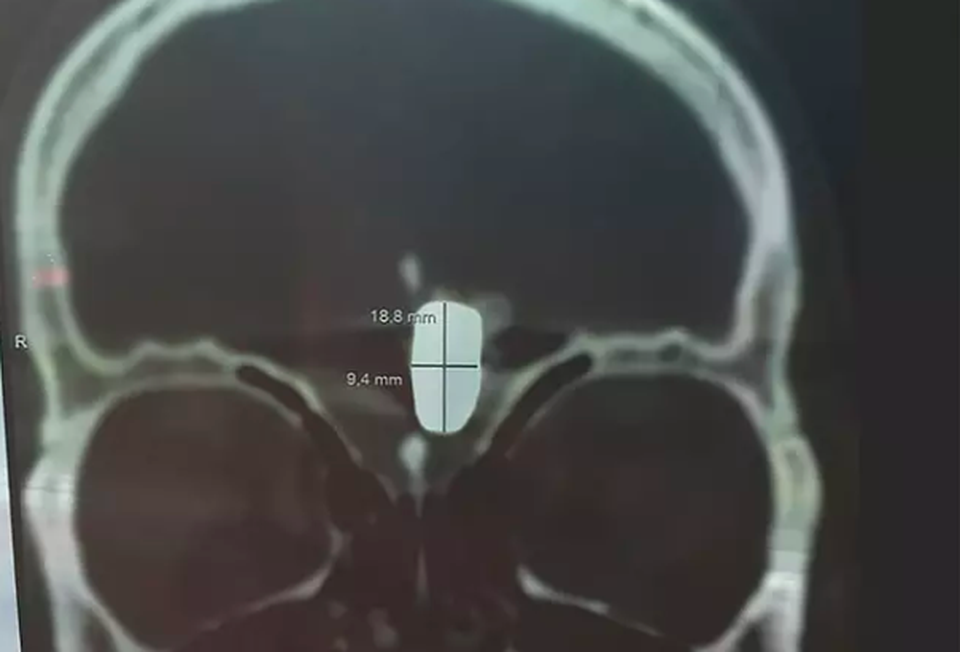

Vladimir Krutov, 36 tuổi, đã được trao cho cơ hội sống sót với tỷ lệ 1/1 triệu sau khi bị bắn vào đầu trong một vụ xả súng băng đảng ở St. Petersburg. Chụp X quang cho thấy viên đạn bị kẹt trong đỉnh đầu của cựu cảnh sát người Nga và các bác sĩ đã từ chối lấy nó ra bởi nguy cơ tử vong do phẫu thuật lên tới 99%.

Sáu bác sĩ phẫu thuật thần kinh hàng đầu đã kiểm tra cho anh và tất cả đồng ý rằng việc loại bỏ viên đạn sẽ dẫn đến tử vong. Vladimir bị cấm bay, bị cấm đi đến phòng tắm hơi nhưng anh vẫn có thể chạy gần 1,6 km, dù bị đau đầu nghiêm trọng.